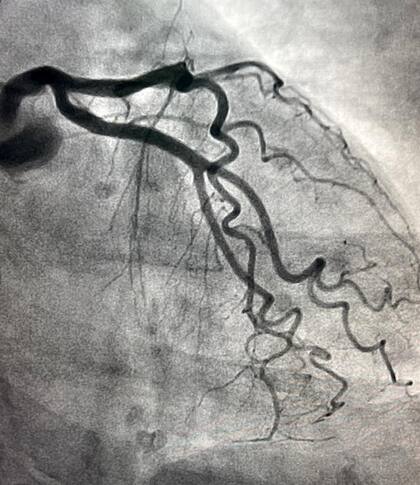

Hasta el Incucai, Fleni o el Garrahan han sufrido últimamente la escasez en alguna medida, pero los más afectados son los centros de salud de menor capacidad económica o del interior. A diferencia de otras industrias a las que el Gobierno autoriza importaciones con plazos de hasta un año, este sector no puede esperar. Es lo que intentaba explicar la semana pasada el reclamo unificado de varias asociaciones de cardiólogos. En la Argentina se hacen por año alrededor de 60.000 angioplastias, un proceso mediante el cual se destapa una arteria, y hay elementos irreemplazables. No hay stents made in Argentina y, si no se importan, todo se agrava. A un paciente con una arteria obstruida en la pierna no le sobran las alternativas: o se la destapa o hay que amputar.

La novedad del caso es que ahora son los propios médicos, no sólo las asociaciones, quienes levantan la voz. Oscar Mendiz, jefe del Instituto de Cardiología de la Fundación Favaloro, publicó el martes de la semana pasada en Twitter la foto de una manifestación callejera de UPCN. “Mientras estos muchachos militan inflación y pobreza al palo; les aviso que no se estresen porque no hay contraste para hacer cateterismo a partir de la semana próxima. Díganles que canten y toquen el bombo despacio porque si se infartan… #SaludEnEmergencia”. Faltaba en ese momento contraste, cuyos frascos de 100 mililitros cuestan unos $18.000. El médico publicó después otro tuit en el que decía haber conseguido algo de producto para esa semana, pero que lo ocurriera a partir de este lunes seguía siendo incierto. Una fuente de una importadora de contraste le contestó este fin de semana a un médico del Hospital Austral: “Hace un par de meses que no tengo producto. Fleni, Swiss Medical, el Cardiovascular. No tenemos contraste ni sabemos cuándo vamos a regularizar la situación”.